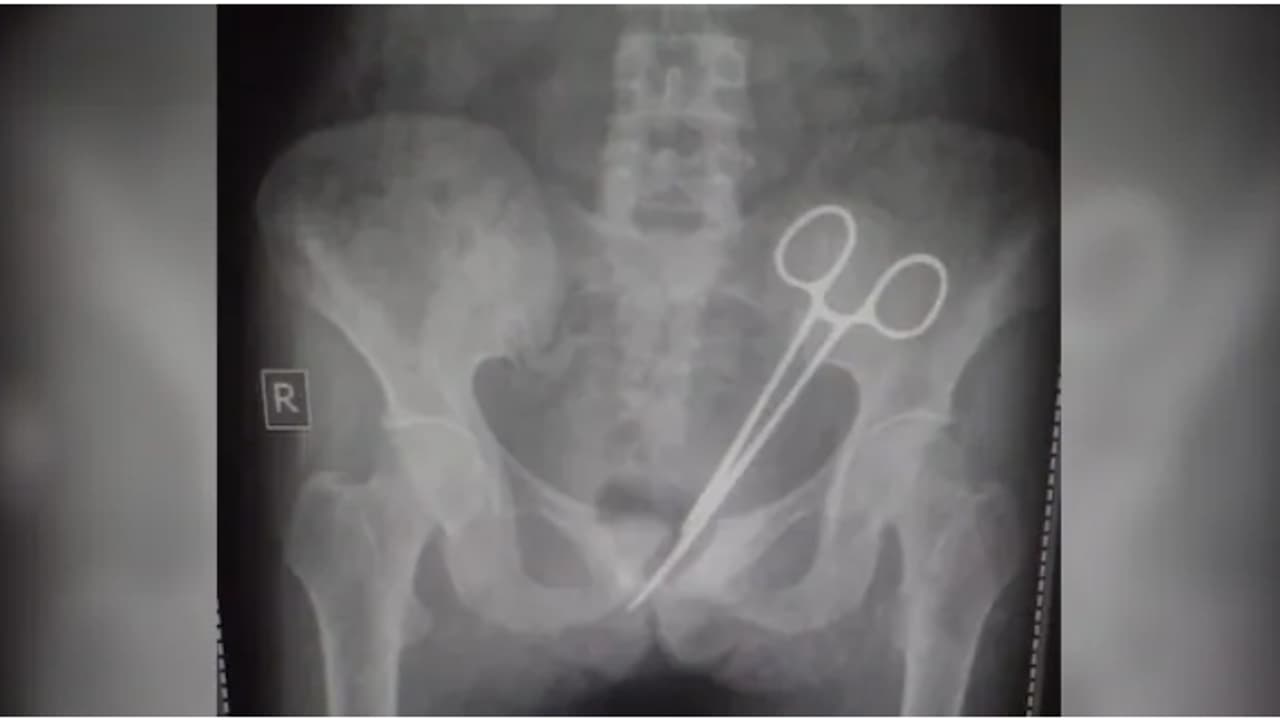

ഗാംഗ്ടോക്: സിക്കിം സ്വദേശിനിയായ സ്ത്രീയെ 12 വര്ഷത്തോളം ബുദ്ധിമുട്ടിച്ച വയറ് വേദനയുടെ കാരണം കണ്ടെത്തിയപ്പോൾ ഞെട്ടി കുടുബം. 2012ൽ അപ്പെൻഡിസൈറ്റിസ് ഓപ്പറേഷന് വിധേയായ ശേഷമാണ് ഇപ്പോൾ 45കാരിയായ സ്ത്രീ ഈ ബുദ്ധിമുട്ടുകൾ അനുഭവിച്ച് തുടങ്ങിയത്. എന്തുകൊണ്ടെന്ന് നിർണ്ണയിക്കാൻ നിരവധി ഡോക്ടർമാർ പരാജയപ്പെട്ടു. ഒടുവില് 2012ല് ശസ്ത്രക്രിയ നടത്തിയ ഡോക്ടര്മാര് വയറ്റില് മറന്നുവെച്ച കത്രികയാണ് എല്ലാ പ്രശ്നങ്ങൾക്കും കാരണണെന്ന് കണ്ടെത്തുകയായിരുന്നു.

അവിടെ എക്സ്-റേ എടുത്ത് നോക്കിയപ്പോഴാണ് വയറ്റില് ശസ്ത്രക്രിയാ കത്രിക കണ്ടെത്തിയത്. മെഡിക്കൽ വിദഗ്ധരുടെ സംഘം ഉടൻ തന്നെ ശസ്ത്രക്രിയ നടത്തി കത്രിക നീക്കം ചെയ്യുകയും യുവതി സുഖം പ്രാപിക്കുകയും ചെയ്തു. എന്നാല് വാര്ത്ത പ്രചരിച്ചതോടെ സംസ്ഥാനമാകെ കടുത്ത വിമര്ശനങ്ങളുയര്ന്നു. ഇതോടെ സംഭവത്തിൽ അന്വേഷണം ആരംഭിച്ചിട്ടുണ്ട്.